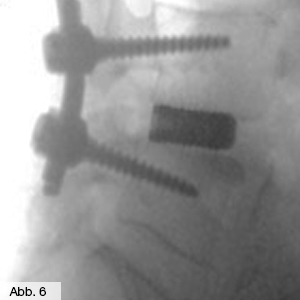

Einen weiteren Schwerpunkt unserer Orthopädie bildet die Behandlung der Instabilität der Wirbelsäule, wie z.B. eines Wirbelgleitens (Spondylolisthese), wobei sich der obere Wirbelsäulenanteil meist gegenüber dem darunterliegenden Wirbelsäulenanteil nach vorn verschiebt. Von diesem Krankheitsbild sind häufig ältere Menschen betroffen. Die konservative Therapie erstreckt sich dabei von der Stützung des Rumpfes mittels einer Rumpforthese über Physiotherapie bis hin zu einer Schmerzbehandlung mittels Infiltrationstherapie (Gabe von Flüssigmedikamenten in die Haut oder tiefer liegende Bereiche) oder PRT (Periradikuläre Therapie, Gabe von Medikamenten direkt an die Nervenwurzel). Bei mangelndem Erfolg der konservativen Maßnahmen entscheiden unsere Fachärzte je nach Symptomatik und Einzelfall, ob eine Operation eine Linderung der Schmerzen bewirken kann – im Falle chronischer Nervenschädigungen oder ausgeprägter statischer Haltungsschäden muss das betroffene Wirbelsegment in einem operativen Eingriff (Spondylodese) reponiert und anschließend versteift werden (Abb. 5 & 6).

Bild Orthopädie Spondylodese

Bild Orthopädie Spondylodese OP